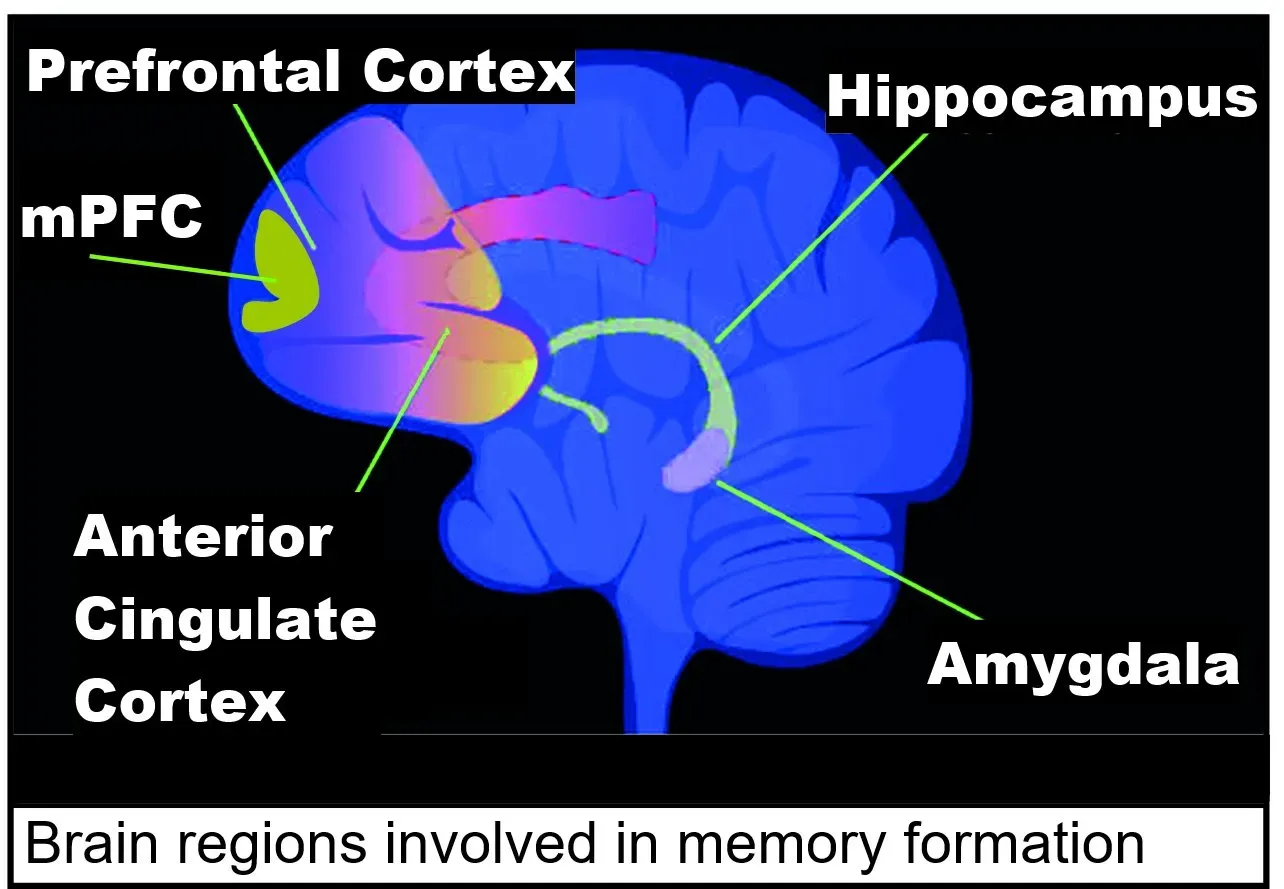

One of the most surprising clues about lifelong brain change came from studies of older adults whose brains were examined after death. Some of these people had the tangled proteins and plaques typically linked to dementia, yet during life they showed little or no memory loss. Their brains seemed to have built up a kind of cognitive reserve, a hidden buffer that helped them function despite damage that, on a scan, looked alarming. That reserve did not appear by magic; it was associated with years of mental stimulation, social connection, and learning.

When neuroscientists looked closer, they saw that aging brains could sprout new connections between neurons, strengthen existing pathways, and recruit fresh regions to handle demanding tasks. In one sense, the older brain behaved like a city that has lost a major bridge but reroutes traffic through side streets and newly built overpasses. The routes may be different from those in youth, but they can still get you where you need to go. That flexibility is the essence of neuroplasticity, and it does not suddenly switch off at age forty, sixty, or even eighty.

The most dramatic evidence for lifelong adaptability often comes from stories of recovery after brain injury or stroke. Older adults who once struggled to move a hand or form simple words have, through months of targeted therapy, regained impressive levels of independence. What is happening in those cases is not simply compensation with the uninjured parts of the body; it is the brain itself rerouting and rebuilding pathways to restore lost functions. Rehabilitation specialists now deliberately design exercises to harness this plasticity, repeating specific tasks until the nervous system strengthens new routes.